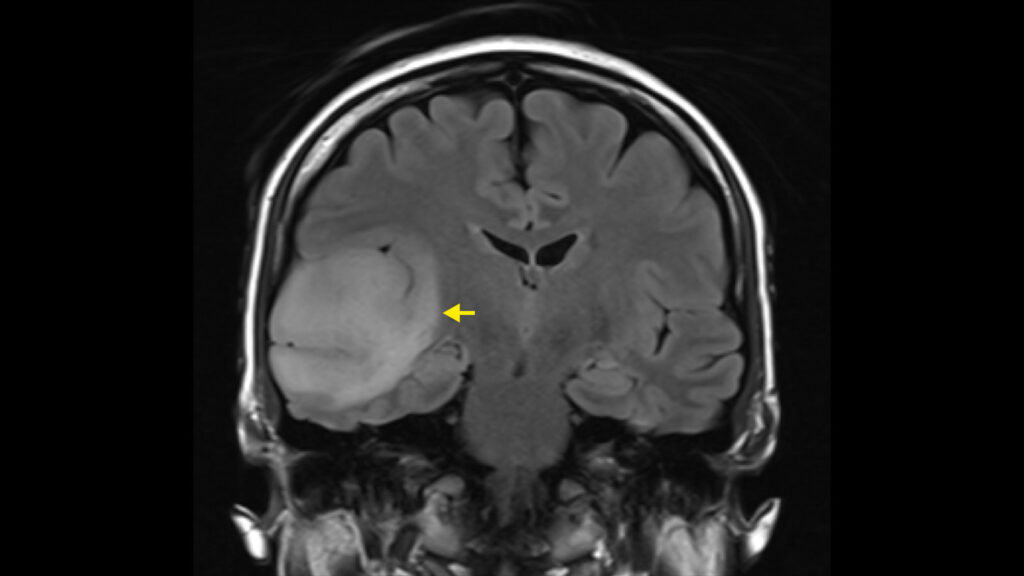

A detailed brain scan highlights the anterior cingulate cortex, the region crucial for detecting errors and resolving conflicts. | Photo by wikimedia.org

The anterior cingulate cortex (ACC) plays a critical role as the brain’s conflict detector. When we face uncertainty or difficult choices, the ACC lights up, signaling internal conflict or potential errors. This region helps us pause, reassess, and make adjustments in our decision process. Its activity is especially pronounced during moments of doubt or when outcomes are unclear, acting as a real-time monitor. More info